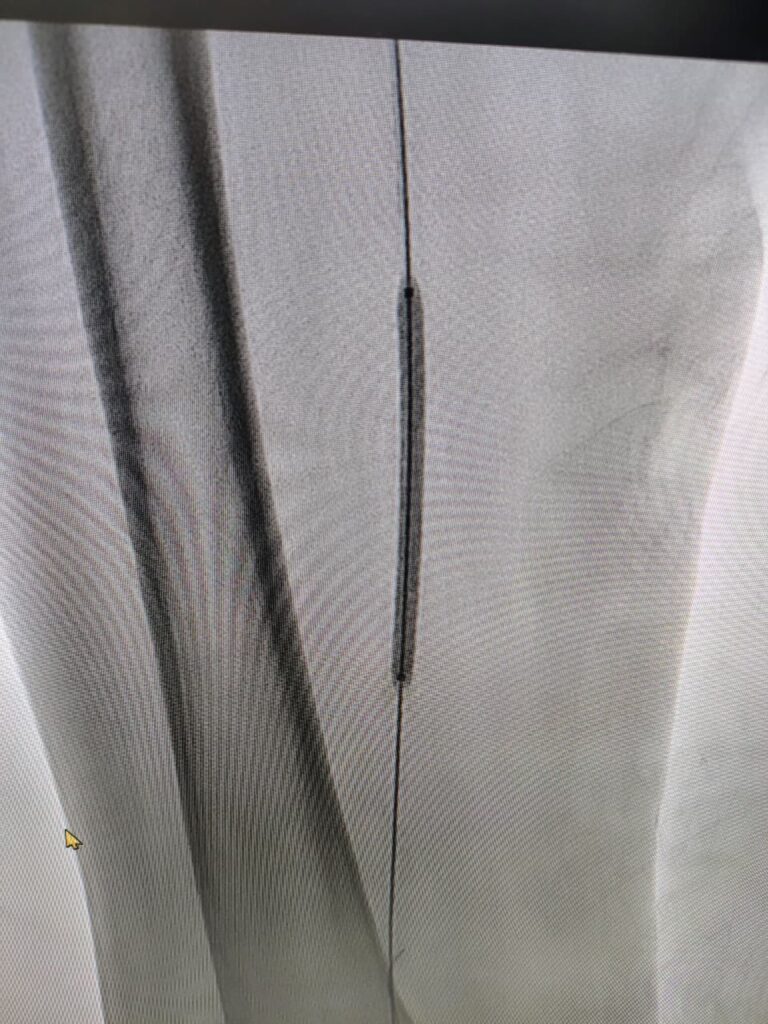

Case 3

A Minimally invasive procedure to open the blocked blood vessels in the lower limbs by Angioplasty